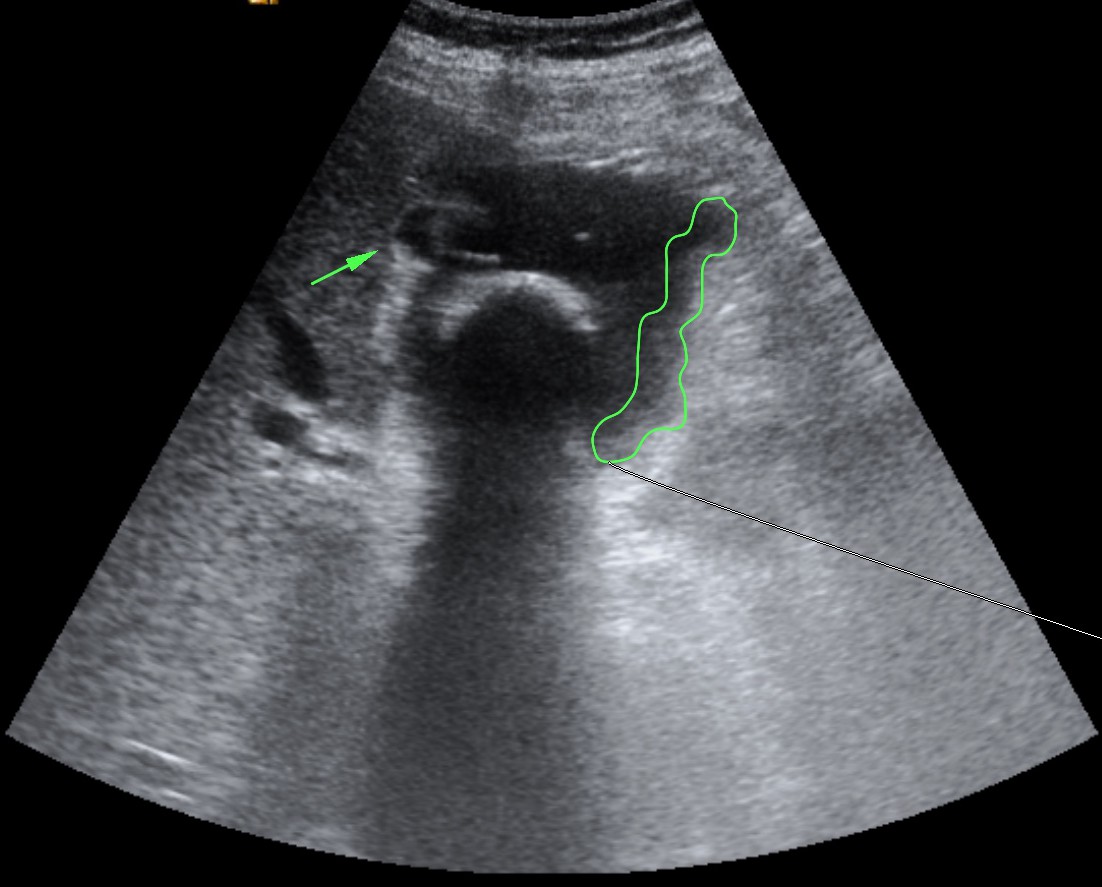

Se realizó posteriormente TC abdominal por mala evolución del paciente:

– La TC se reserva para pacientes con dudas diagnósticas o con discrepancia clínico ecográfica. Se obervarán los mismos hallazgos que en la ecografía, además del aumento de densidad de la pared de la vesícula, del parénquima hepático o especialmente la presencia de otras complicaciones.